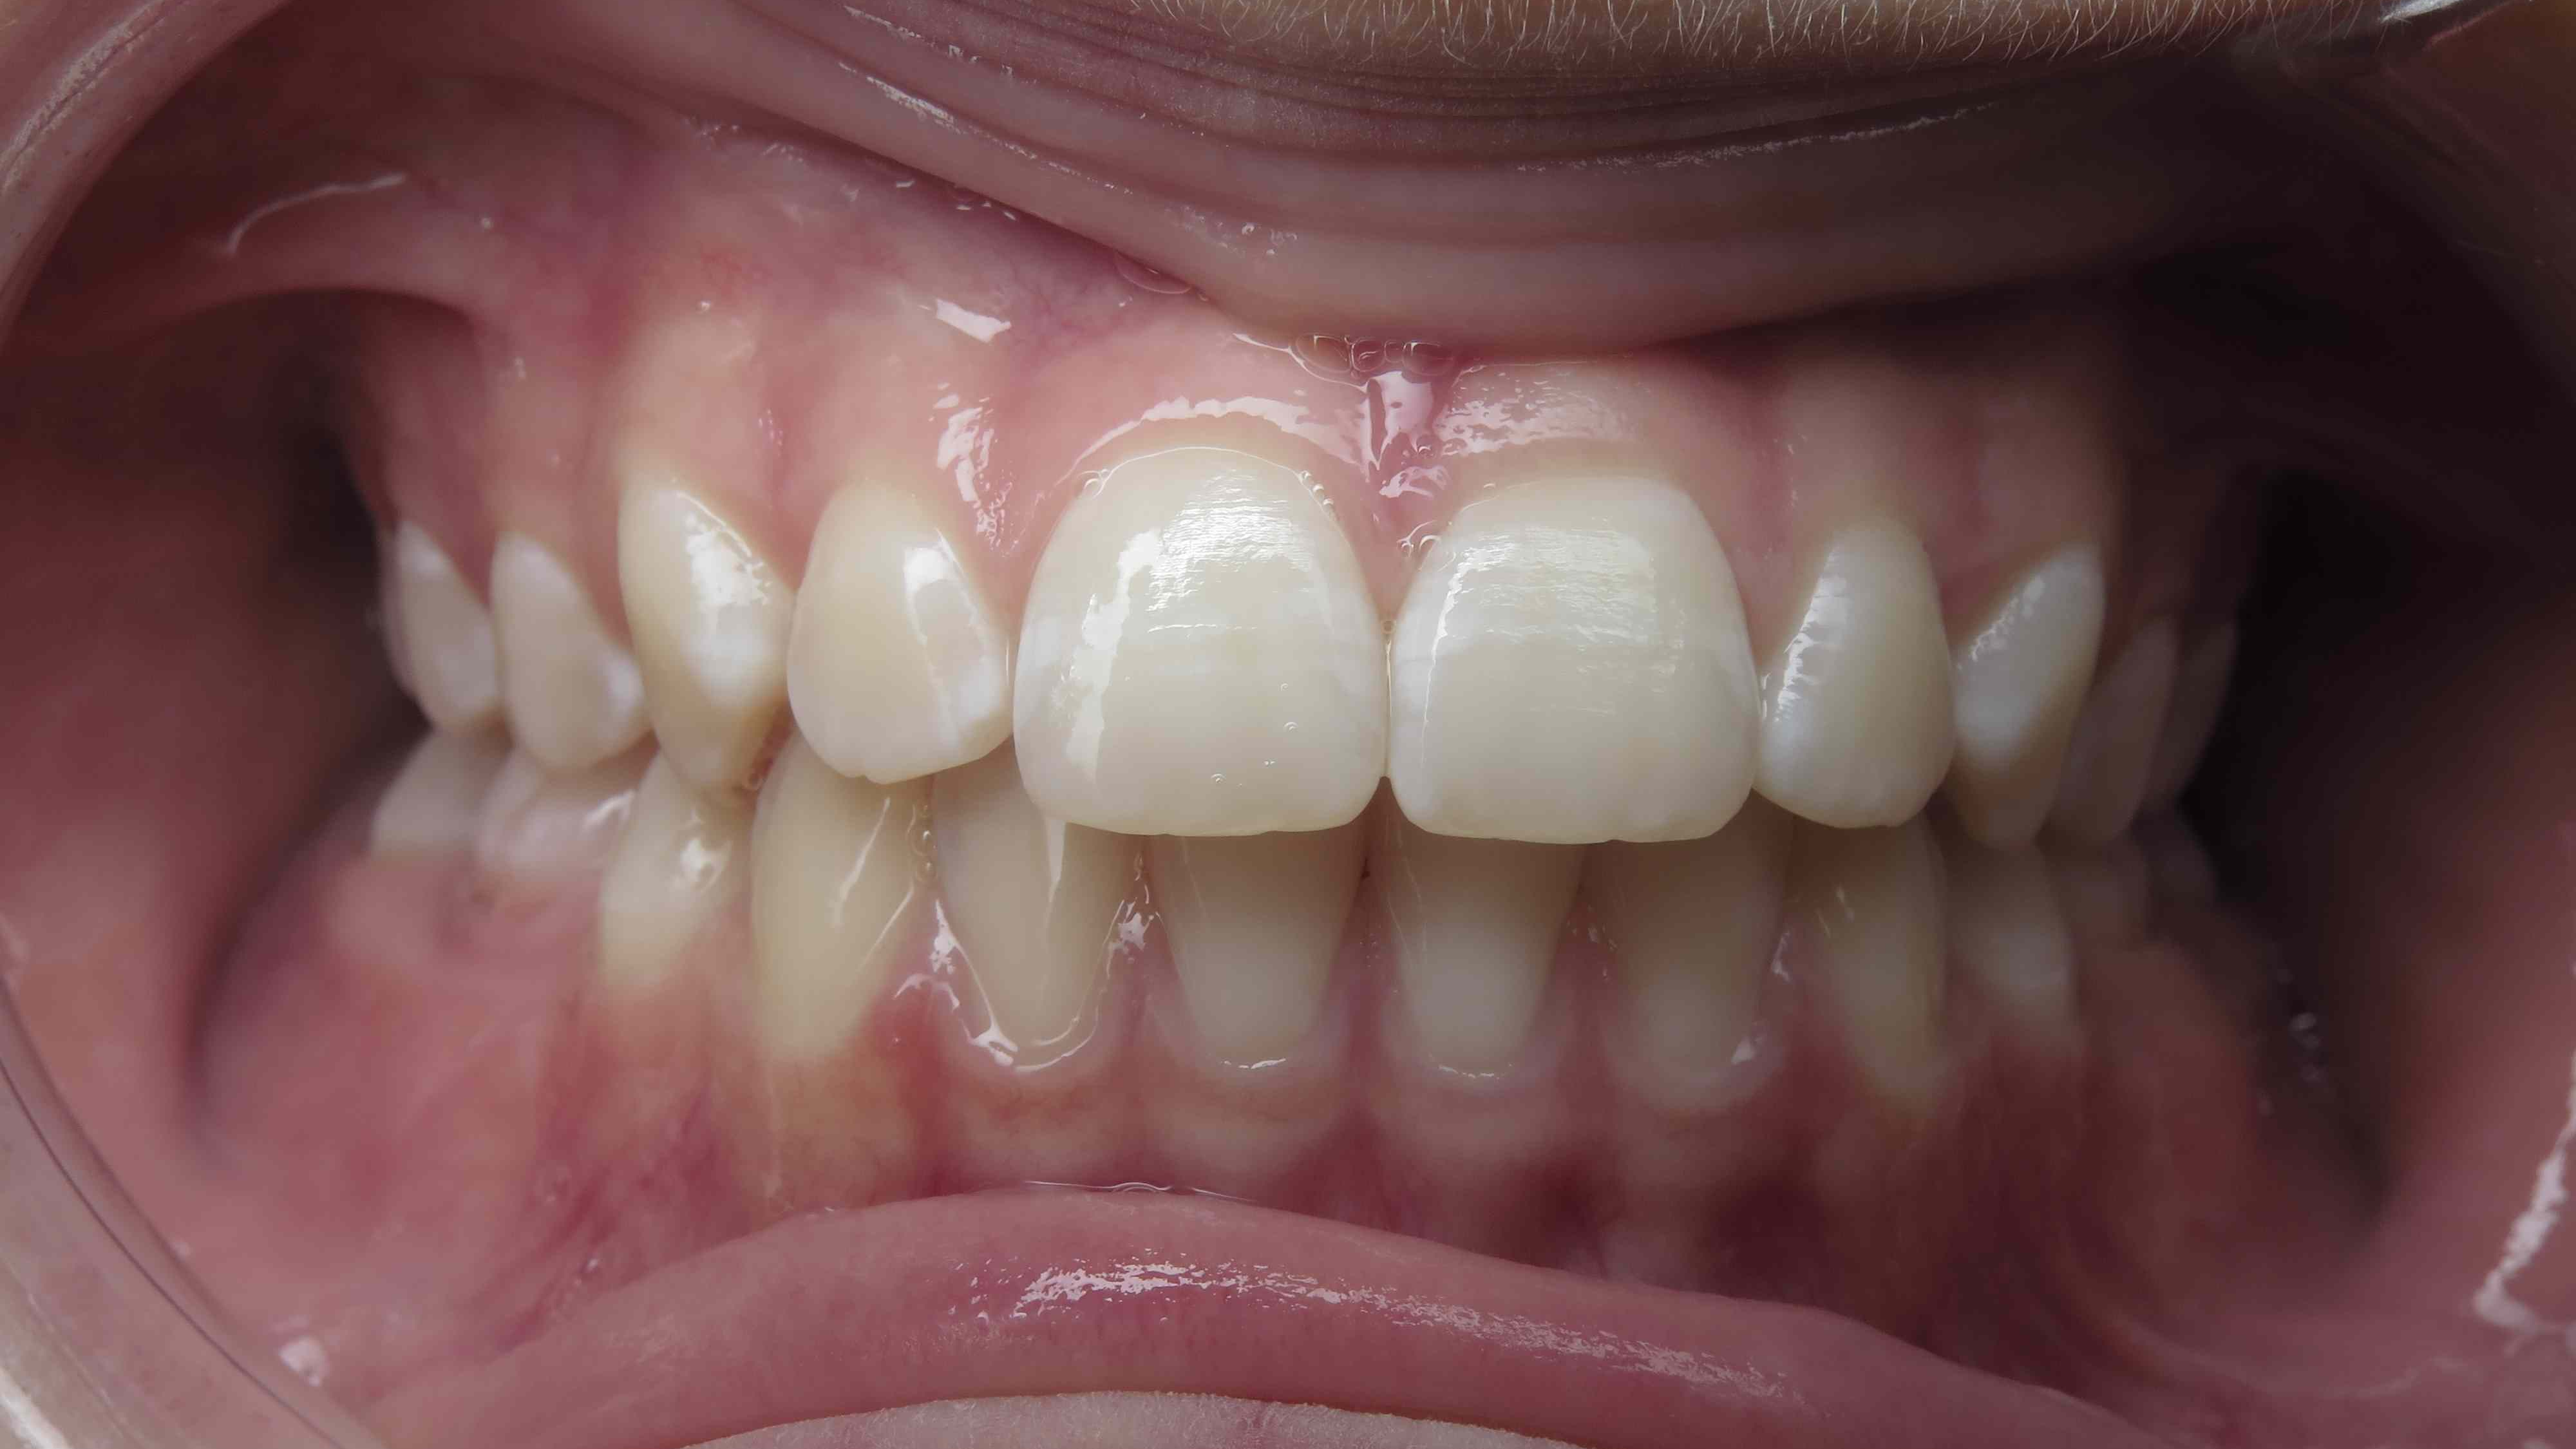

appareillage multibagues traitement en cours

bilan début et en cours de traitement